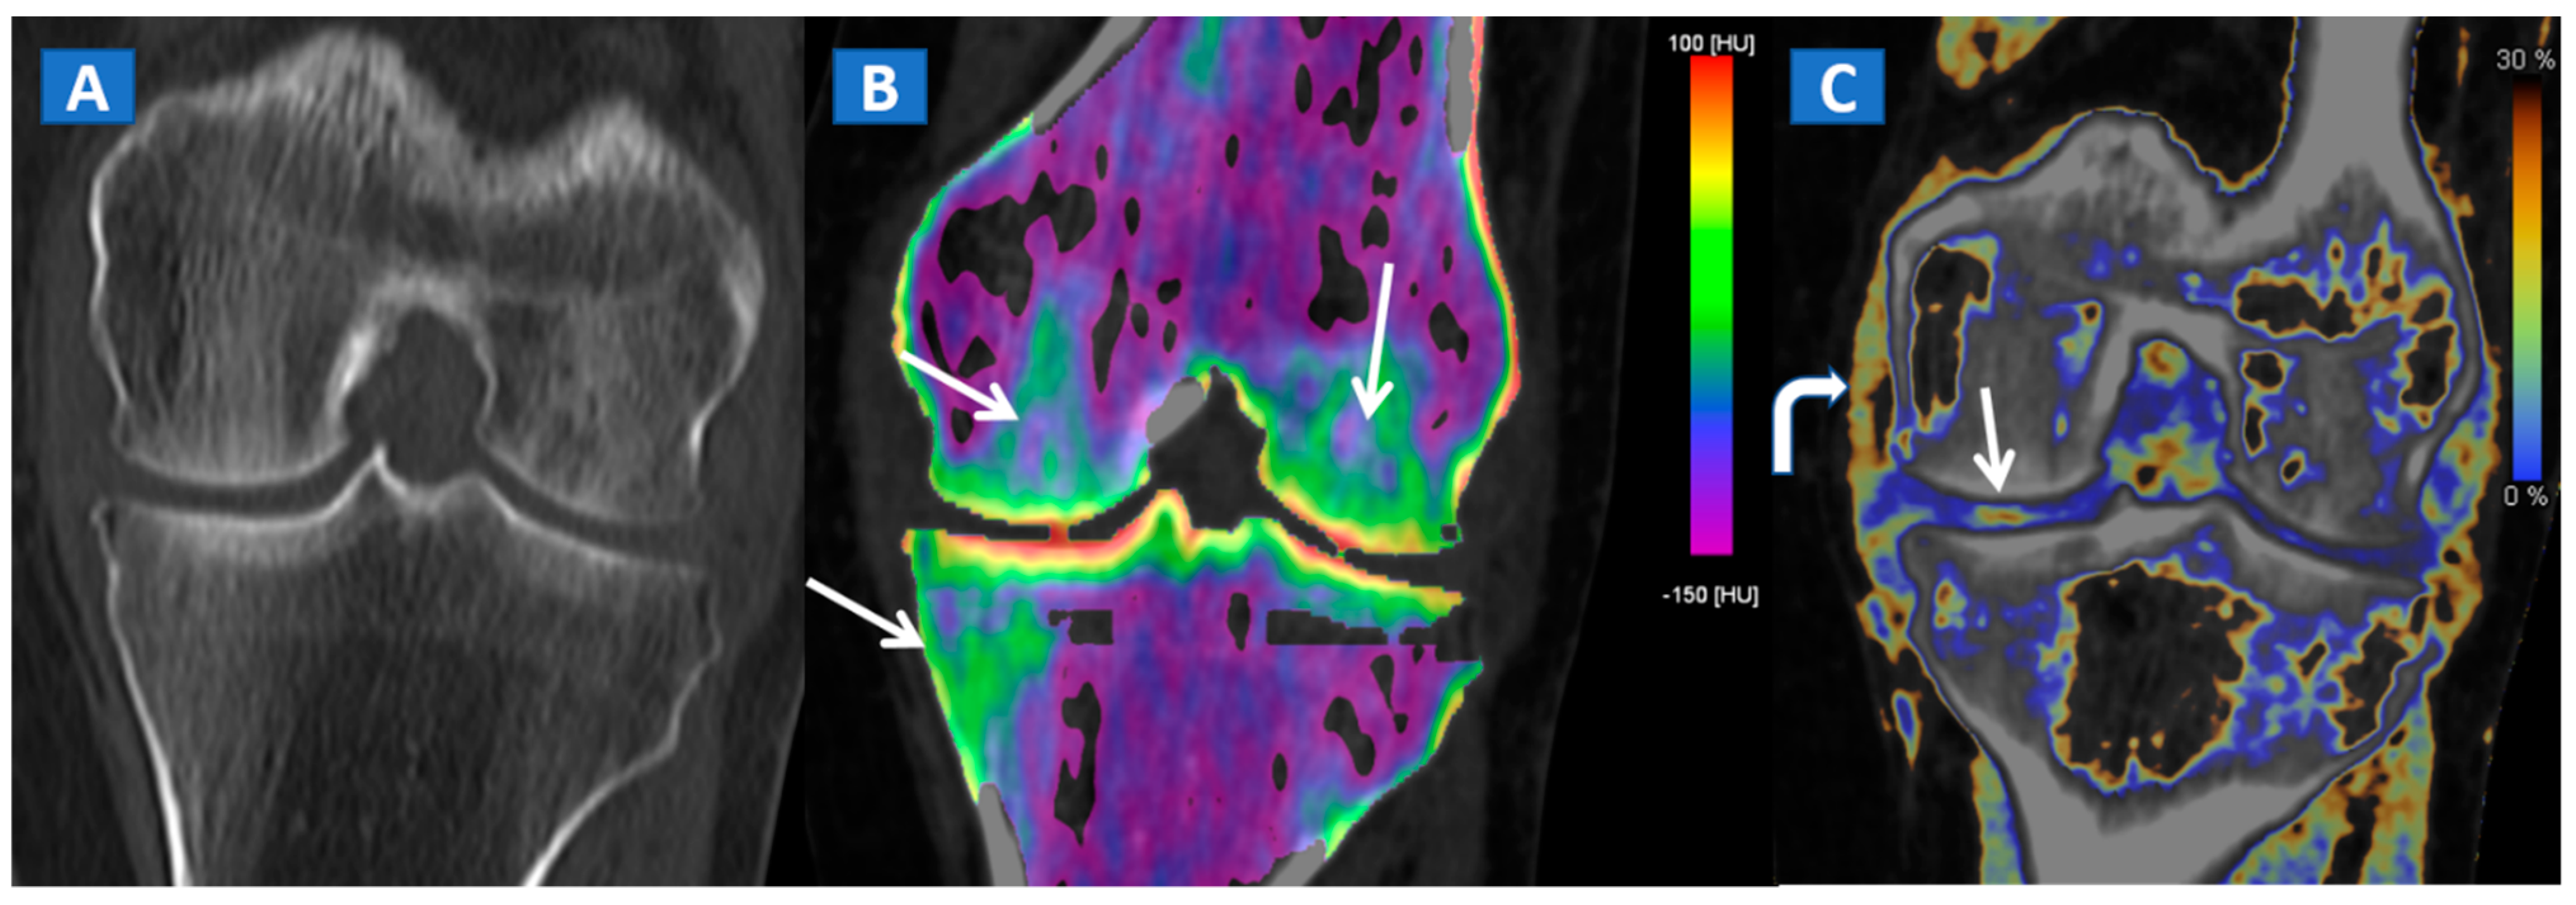

Figure 6.

A 65-year-old female with a post-traumatic medial menisci rupture and diffuse BME. On the standard 1 mm reconstructed coronal CT image (A), there are no signs of fracture. On the corresponding 2D 1 mm reconstructed 2D DECT image (B), the BME appears more pronounced on the femoral condyles and on the medial tibial plateau (arrows). By using different color-coding (C), it was possible to identify a rupture of the medial menisci (straight arrow), with thickening and oedema of the medial collateral ligaments (curved arrow).